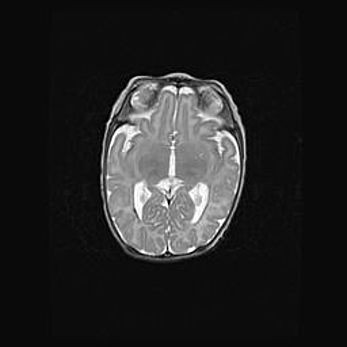

Наружная гидроцефалия с возможной атрофией височных областей.

Возраст: 28 дней

Вес: 3670 г

Пол: мужской

Окружность головы: 38 см

Срок гестации: 40 недель

Гидроцефалия головного мозга у новорожденных – это заболевание, которое характеризуется скоплением избыточного количества спинномозговой жидкости в желудочковой системе головного мозга в результате затруднения её перемещения от места выработки к месту поглощения в кровеносную систему или вследствие нарушения абсорбции. При открытой наружной форме гидроцефалии у новорожденных расширяются и переполняются субарахноидные пространства.

При нормотензивных  формах,  которые,  как  правило,  являются  следствием  перенесенных ишемических  повреждений  паренхимы  мозга,  возможно  сочетание микроцефалии  с нормотензивной гидроцефалией. В основе данных изменений лежит атрофия больших полушарий с преимущественной  локализацией  в  лобно-височных  областях.